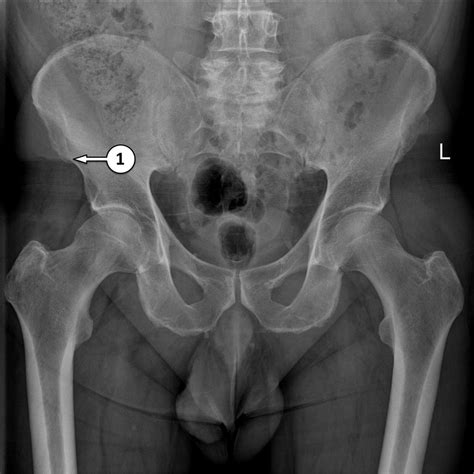

Interpreting a Normal Hip X Ray

Interpreting a Normal Hip X Ray requires a trained eye. Radiologists look for specific features to determine the health of the hip joint. Key elements include:

• Bone Density: The density and structure of the bones should appear uniform and without any fractures or lesions.

• Joint Space: The space between the femoral head and the acetabulum should be consistent and without narrowing, which could indicate arthritis.

• Alignment: The femoral head should be properly seated within the acetabulum, and the neck of the femur should align correctly with the shaft.

• Soft Tissues: The surrounding soft tissues should appear normal, without any swelling or abnormalities.